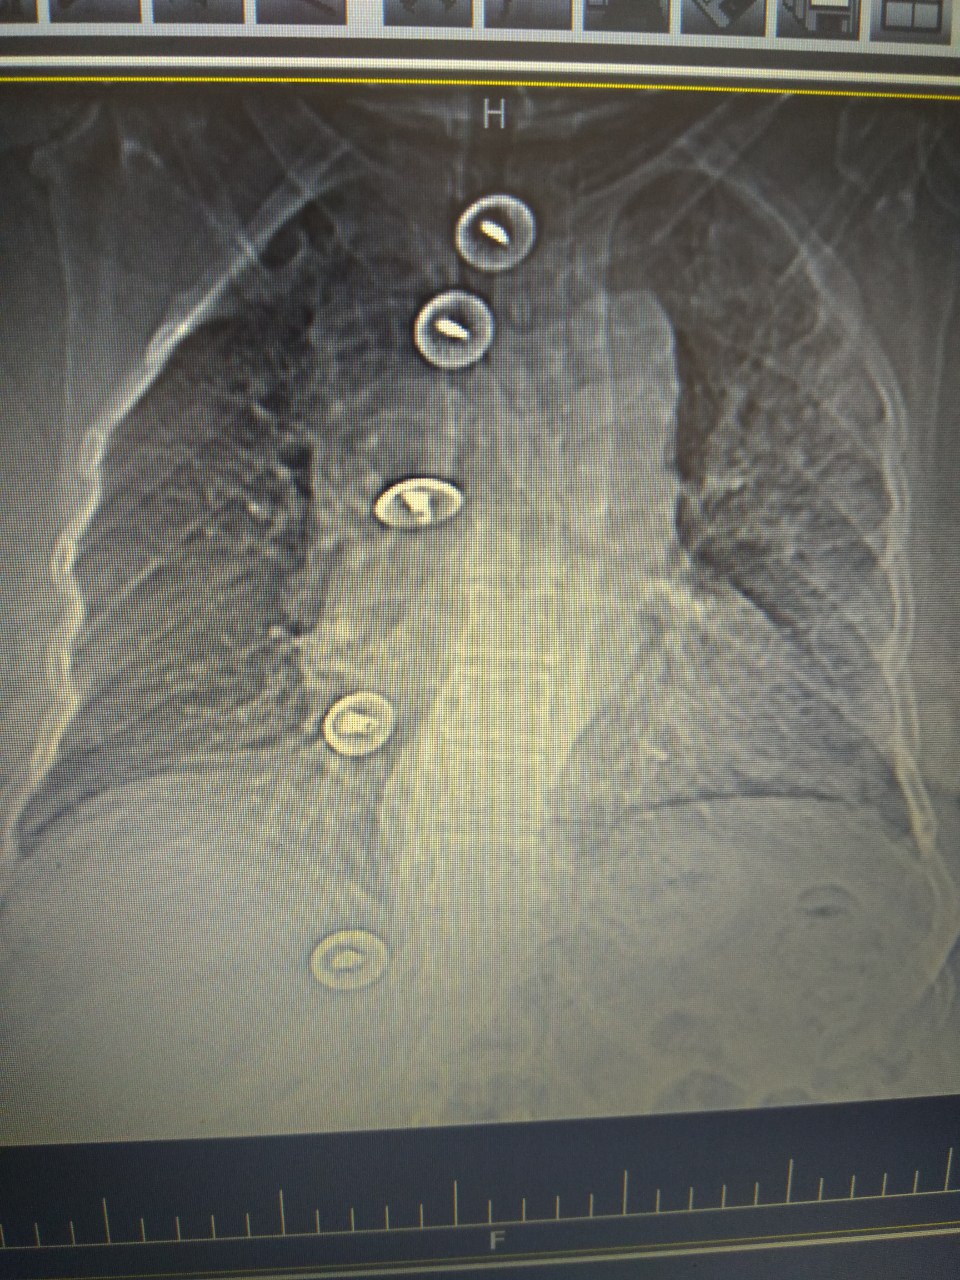

Подскажите, какой позвонок здесь лишний?

L6

Переходный люмбосакральный